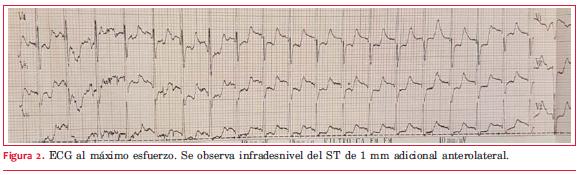

Al máximo esfuerzo (

Ante el resultado de la PEG se decide realizar centellograma de perfusión miocárdica MIBI sensibilizado con esfuerzo ergométrico. El ECG basal del estudio muestra una repolarización ventricular normal. El ECG al máximo esfuerzo (